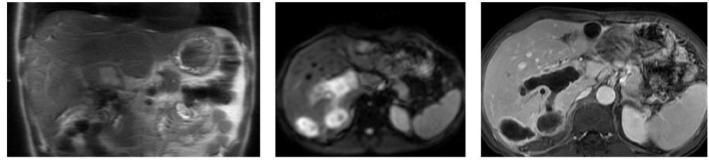

肝包虫囊肿破入门静脉:一种罕见的并发症。

Hydatid cyst of the liver rupturing into the portal vein: A rare complication.

Hydatid cyst of the liver is a zoonosis caused by parasite , which remains highly prevalent in Morocco. Current medical imaging modalities, particularly ultrasonography (US) and computed tomography (CT), facilitate rapid and accurate diagnosis, enable effective treatment possibilities and allow for easy follow-up. Complications are typically dominated by infection and rupture, especially in the bile ducts, peritoneal cavity, and chest. Dissemination and development within vascular structures, especially the portal vein, are much less common. This underscores the significance of our case, which illustrates this rare complication of hydatid cyst of the liver.

摘要

肝包虫囊肿是一种由寄生虫引起的人畜共患病,在摩洛哥仍然高度流行。当前的医学成像方式,尤其是超声检查(US)和计算机断层扫描(CT),有助于快速准确的诊断,提供有效的治疗可能性并便于随访。并发症通常以感染和破裂为主,尤其是在胆管、腹腔和胸部。在血管结构内,尤其是门静脉内的播散和发展则要少见得多。这凸显了我们病例的重要性,该病例说明了肝包虫囊肿这种罕见的并发症。